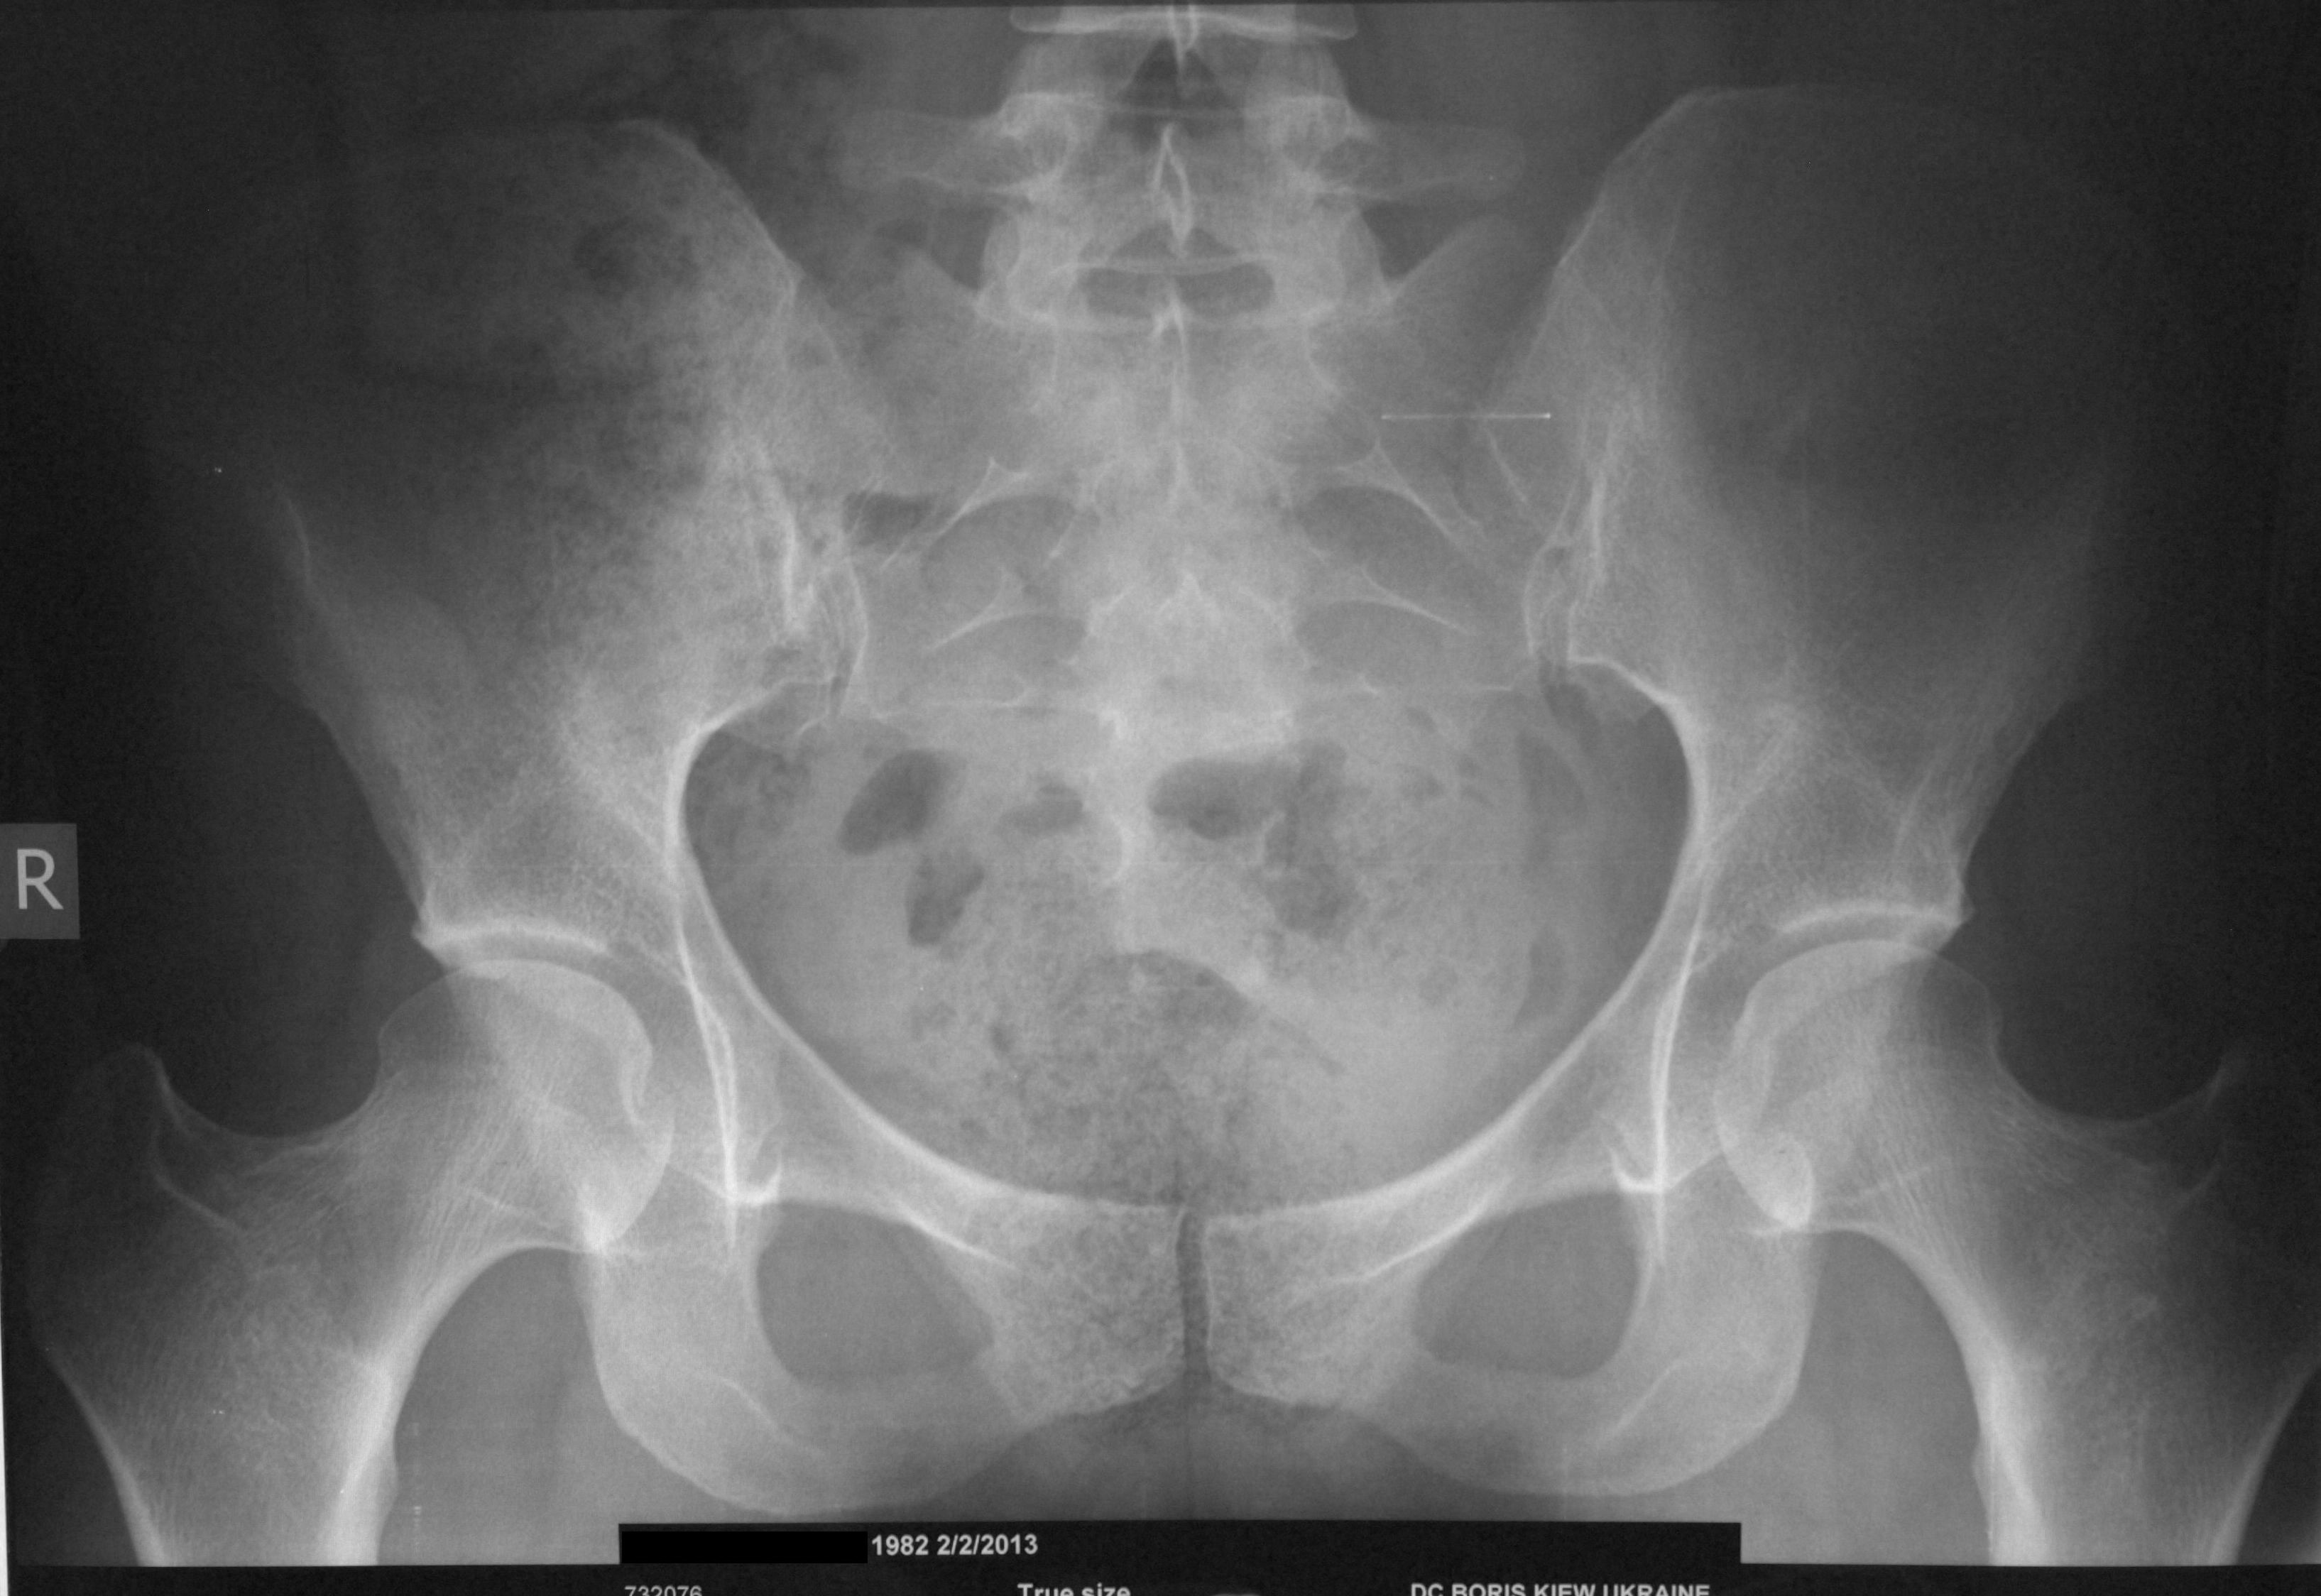

Копчик

Копчик, или хвостец, формируется при слиянии позвонков, и представляет собой остаток хвоста, который имеется у других млекопитающих.

Было высказано предположение, что копчик помогает закрепить небольшие мышцы и поддерживать тазовые органы. Тем не менее, имели место многочисленные медицинские случаи, когда копчик был удален хирургическим путем без каких-либо негативных последствий.

Некоторые медицинские случаи описывают младенцев, которые рождаются с удлиненным копчиком. Сегодня от такого необычного «хвоста» можно легко избавиться хирургическим путем, но в Средние века считалось, что такая примета указывает на связь с дьяволом, и таких случаях мать вместе с ребенком казнили.